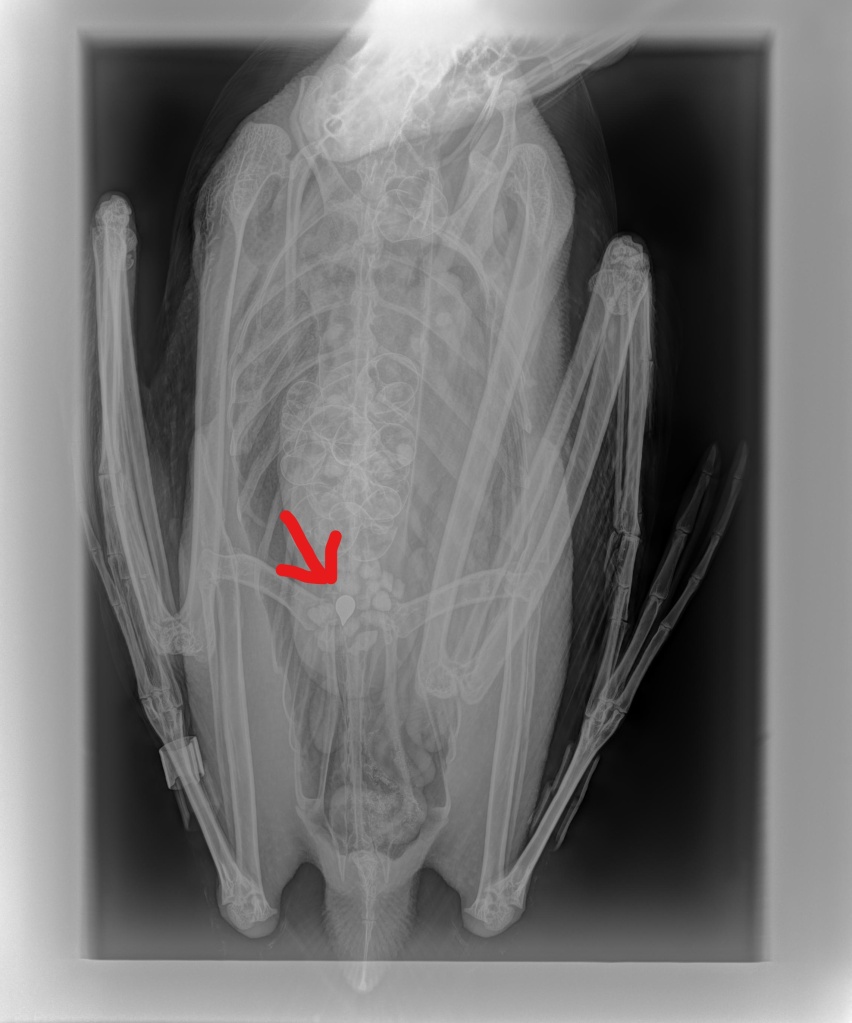

We drew blood for a blood lead level test hoping for good news. While we were waiting for the test to finish, we took a couple x-rays. Both diagnostics confirmed our worst suspicions.

The x-ray revealed what appeared to be a jig head in its stomach. This was the likely culprit. In these situations, removing the source of lead in the digestive tract is the only way to keep lead from continuing to enter the bird’s system. We were the first rehabbers in the state to use endoscopy to accomplish removal of fishing tackle from loons. (See Loon Endoscopy blog and the video).The human gastroenterologist who donated use of his equipment and skill has long since retired meaning that is no longer an option. Most rehabbers and their veterinarians “gavage” the item out of the stomach. This is accomplished by anesthetizing the bird and “flushing” the entire stomach contents from the bird.